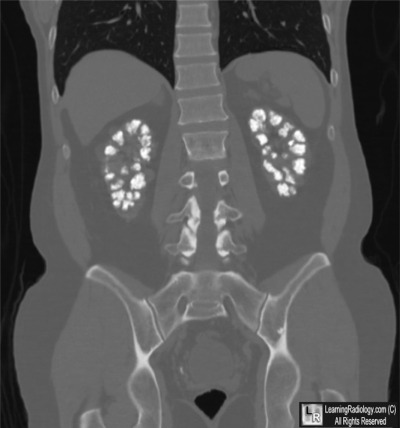

Additional Image-Coronal CT of Abdomen

Coronal CT of Abdomen

5. Medullary Nephrocalcinosis

Medullary Nephrocalcinosis

- Increased calcium content of kidneys

- Usually applies to a generalized, rather than localized, increase in renal calcium content

- Macroscopic nephrocalcinosis is nephrocalcinosis visible without magnification discovered by radiography, ultrasonography, or at autopsy

- Macroscopic nephrocalcinosis can affect either cortex or medulla

- Medulla more common